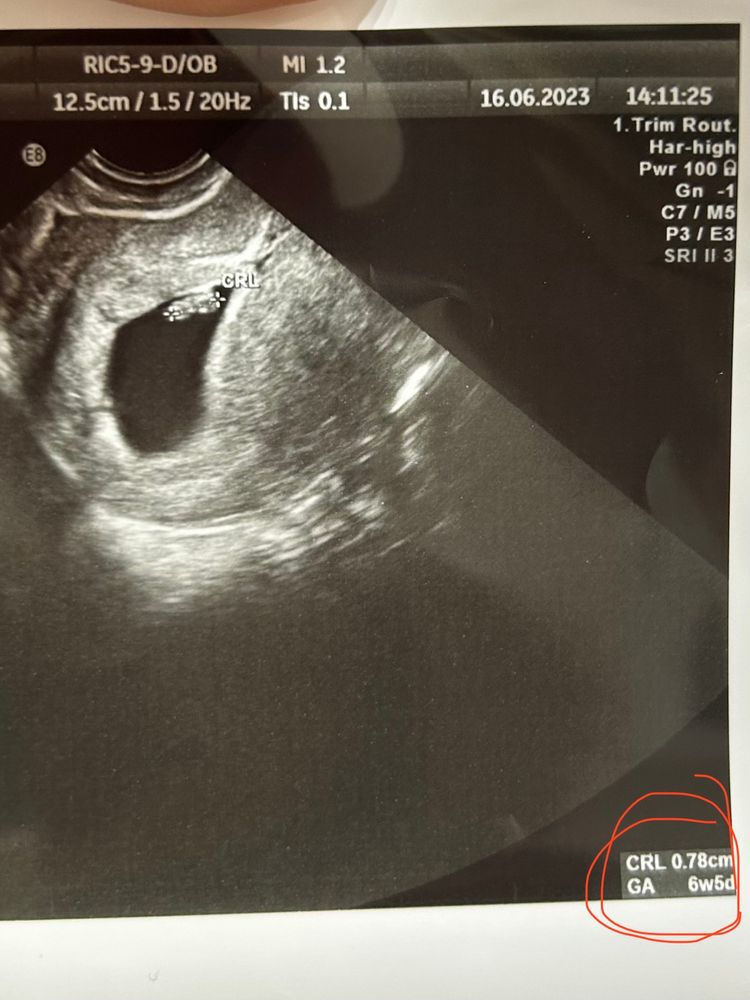

Вопросы про УЗИ, обследования и анализы: что, где, как, когда?Сегодня была на узи, в целом и цифры из описания (текста) +-по сроку подходят, и на самом снимке ктр обозначен, он ближе к правде должен быть, но почему вообще отличаются🤔 картинки ниже

ктр 0,78 или 0,6?

Меряют несколько раз среднее пишут. У вас написано 6,3-7 недель. На этом сроке это нормальная погрешность ибо маленький ещё малышик. Уточняют срок на первом скрининге.